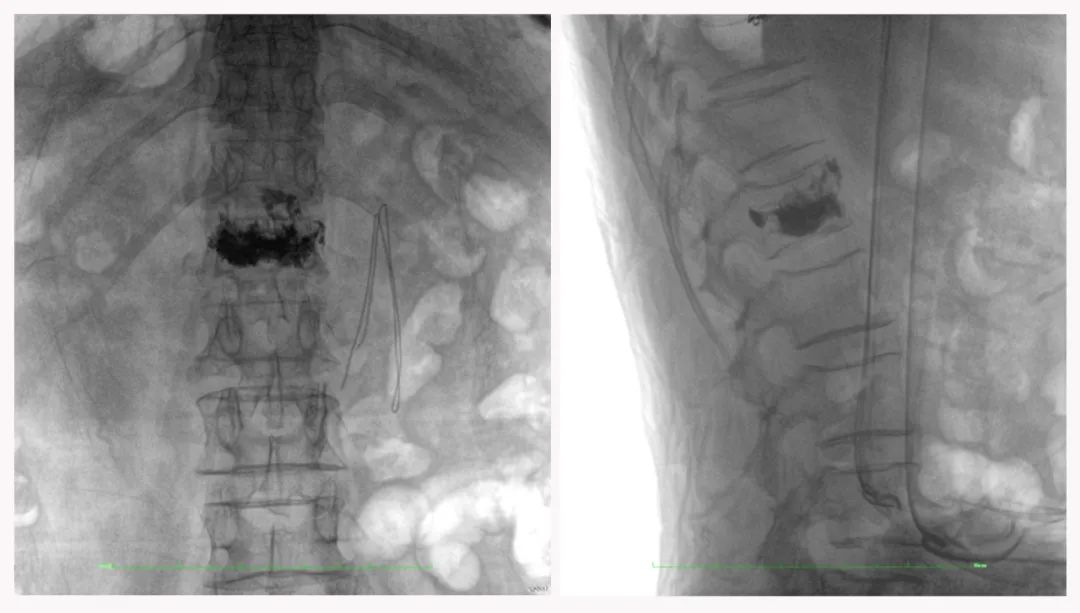

二维正侧位影像

三维“类CT”影像

在临床使用中,三维C形臂能看到二维影像所观察不到的信息:

病例1:右侧股骨远端骨骺骨病(13岁)

二维影像看不到病灶点

三维切面影像可以看出病灶点